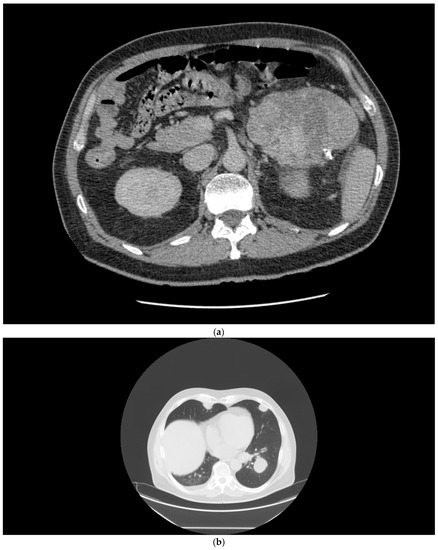

A 68-year-old man presented in March 2020 with a large tumor of the right kidney with synchronous metastases to the lungs, mediastinum, left adrenal gland, and extensive retroperitoneal lymphadenopathy (Figure 1a). The medical history was otherwise unremarkable. The patient underwent cytoreductive nephrectomy regardless of the presence of poor prognostic features according to the IMDC, including anemia, hypercalcemia, thrombocytosis, interval to therapy initiation, and Karnofsky performance status (KPS) 2, in April 2020. Histological examination confirmed a renal cell carcinoma with sarcomatoid and rhabdoid features. In May 2020, the patient received four cycles of nivolumab (3 mg/kg) plus ipilimumab (1 mg/kg) given every three weeks. Within a few weeks of therapy, the patient reported significant relief. Lab tests, including blood count and serum calcium, normalized, and KPS improved to 0. A follow-up CT scan showed partial response in all evaluated lesions (Figure 1b). The only adverse event was itching, that did not require any intervention. The patient continued with nivolumab monotherapy at a 480 mg flat dose until April 2021, when the therapy was interrupted due to Common Terminology Criteria for Adverse Events (CTCAE) grade 3 dermatitis. Systemic prednisone was initiated at 0.5 mg/kg, and the rash decreased within a few weeks. Upon improvement, the therapy with nivolumab was reintroduced. After 25 months, in June 2022, the patient remains on therapy, with a minimal residual tumor on CT scan and no additional adverse events.

Figure 1.

(a) Patient 1, pretreatment CT of the chest demonstrating lung metastases. (b) Patient 1, marked tumor reduction after the combination regimen of ipilimumab with nivolumab.